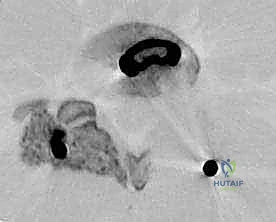

في هذه التقنية، يتم الوصول إلى العمود الفقري من الخلف مباشرة. يقوم الجراح بإزالة جزء من العظم (الصفيحة الفقرية Laminectomy) للوصول إلى القناة الشوكية. يتم سحب الأعصاب برفق إلى الجانبين للوصول إلى القرص التالف وإزالته، ثم يتم إدخال "أقفاص" (Cages) مدعومة بطعوم عظمية من كلا الجانبين.

تقنية TLIF (الاندماج الفقري القطني عبر الثقب)

تُعد TLIF تطوراً لتقنية PLIF. بدلاً من الدخول مباشرة من المنتصف وسحب الأعصاب بشكل كبير، يتم الوصول إلى القرص الغضروفي من جانب واحد عبر "الثقبة" (Foramen) - وهي الفتحة التي يخرج منها العصب.